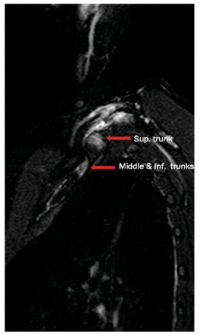

An initial MRI of her left brachial plexus showed increased T2 signal in the C8 root, superior trunk, and posterior cord. Over the next 2 years several treatments were tried, including a course of prednisone, baclofen, and gabapentin, none of which improved her symptoms. A trial of an ultrasound-guided botulinum toxin injection to the left anterior scalene was also undertaken, which provided no benefit. A subsequent MRI of the brachial plexus was ordered, but now with her arm in full abduction. This MRI (Fig. 1) showed that the superior trunk separates from the inferior and middle trunks and takes a 90° turn and kinks as it travels toward the costoclavicular space, where it has mildly elevated T2 signal. It also showed the posterior cord travelling through the proximal costoclavicular space, which is markedly narrowed compared with the other side, and has an increased T2 signal here compared with the arm in the neutral position.

Fig. 1. Sagittal STIR MRI sequence with shoulder abducted showing superior trunk separating from the middle and inferior trunks, and kinking toward the costoclavicular space.